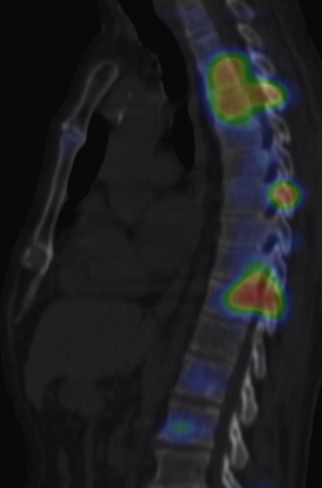

The most common indication of bone scintigraphy is the evaluation of bone metastasis. (Figure 5.)

5. Multiplex bone metastases. Bone scintigraphy, anterior (a) and posterior (b) whole body scans. SPECT-CT sagittal plane, fusion image (c) and CT image (d). Obvious bone structural changes cannot be identified on the CT scan yet.

The examination is appropriate for staging a malignant process and following-up bone metastases. It is clinically most suitable for lesions that frequently present bone metastasis, primarily in case of prostate-, breast-, lung cancer and neuroblastoma. It is, however only indicated in cases where the soft tissue involvement of the tumor is big enough to suggest a higher incidence of bone metastasis; before radical surgeries and for the selection of patients who would benefit form a palliative radionuclide therapy. Otherwise, scintigraphy is advisable in case of any primary tumor, if the suspicion for metastasis is raised, e.g.: bone pain, pathologic radiological or lab results (elevated serum ALP and tumor marker levels). Bone metastases in most cases are located in bones that contain red bone marrow (skull, vertebrae, ribs, sternum, pelvic bones and the proximal bone segments of the limb) and usually show a multiplex appearance. Activity increase can be seen typically, metastases that cause activity decrease are rare; they could occur in cases of thyroid gland tumor, renal carcinoma, lymphoma and multiple myeloma. Solitary lesions or a few lesions only, due to the aspecific nature of the examination, cause a differential diagnostic problem in many cases, for example vertebral degenerative processes can mimic metastatic activity. Equivocal lesions usually require further, targeted radiological investigations. A negative X-ray examination does not rule out the possibility of a metastatic lesion, since the isotope scan is more sensitive. Therefore, it is possible that it could already be detecting an existing metastasis, while X-ray is still insensitive and unable to show the lesion. (Figure 5.)